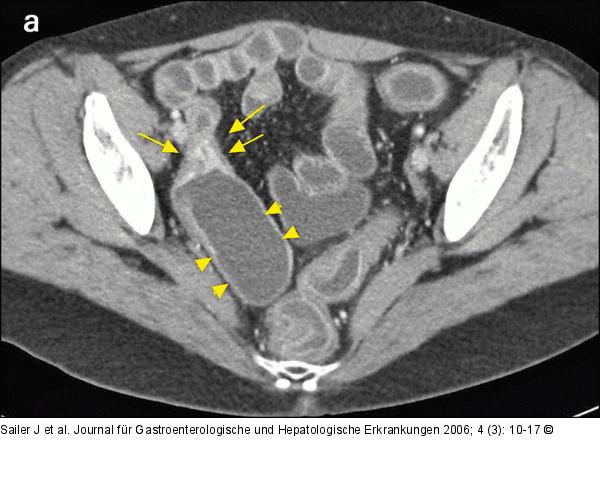

Abbildung 4a-b: Morbus Crohn-Rezidiv Morbus Crohn-Rezidiv im neoterminalen Ileum nach Ileocoecalresektion. CT-Enteroklysma eines 38jährigen Patienten zeigt an der Anastomose eine höhergradige kurzstreckige Stenose mit Wandverdickung und verstärkter Kontrastmittelaufnahme (Pfeile), begleitende prästenotische Dilatation (Pfeilspitzen). |

Morbus Crohn-Rezidiv im neoterminalen Ileum nach Ileocoecalresektion. CT-Enteroklysma eines 38jährigen Patienten zeigt an der Anastomose eine höhergradige kurzstreckige Stenose mit Wandverdickung und verstärkter Kontrastmittelaufnahme (Pfeile), begleitende prästenotische Dilatation (Pfeilspitzen). |